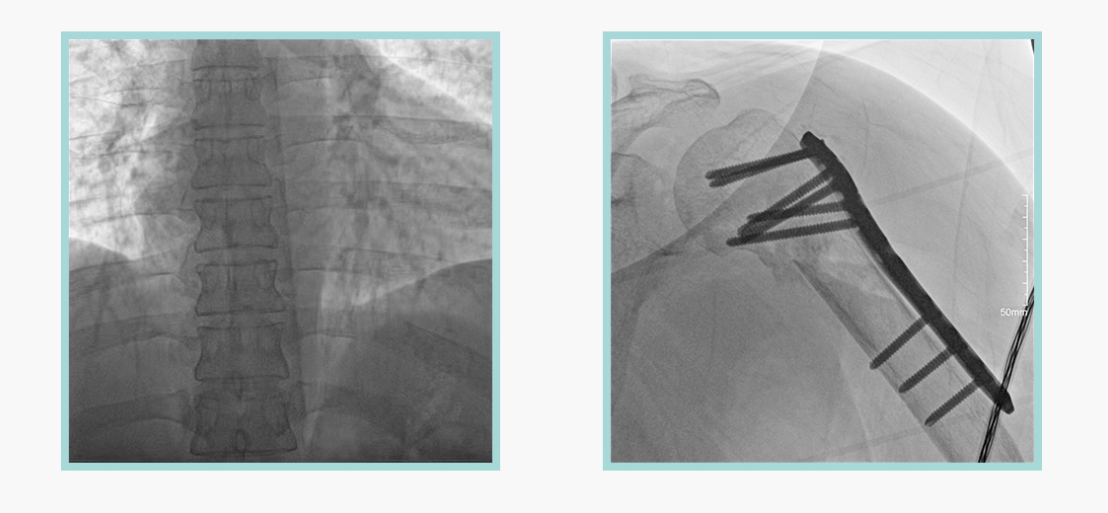

作为全球X线机的主要参与者,德赢VWIN科技在数字化X线产品线实现全线动态化之外,在移动C臂X光机产品线领域推出全新平板移动C臂产品:悦画。随着国家“千县工程”提升基层医疗卫生服务能力,外科对于手术介入引导设备的需求剧增。对于一台优秀的移动C臂X线机而言,如何保证最优质影像的同时,最大程度降低X线的辐射剂量,并在满足临床手术引导/定位的同时,最大程度的保护临床手术的医务人员,是悦画最为关切的问题。

此外,骨科手术时间平均时长约为45分钟左右时间,长期的X线透视或摄影曝光剂量将对临床手术与操作医务工作者造成难以评估的健康风险,悦画通过支持摄影曝光参数的自主调节,可以保证在最低剂量水平下输出满足临床手术定位与引导所需要的影像质量,相较于市面上的固定曝光参数配置移动C臂,自主参数调节设计的曝光功能设计,可以大幅减少医务工作者的X线辐射剂量。

不仅如此,悦画在产品的剂量安全管理上,还支持DAP剂量实时显示与统计功能。为了减少误操作的X射线曝光,悦画具有X射线锁定保护功能,在摄影曝光停止后立即进行X射线曝光锁定,解锁后才能支持继续曝光,减少以往临床过程中医务工作者因为误操作所导致的额外X射线辐射。